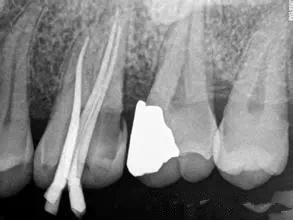

而且,這個(ge) 時候還要打個(ge) 樁加固一下,一般來說纖維樁就夠了。